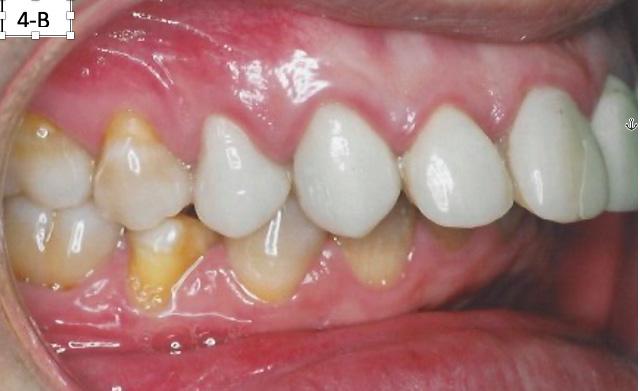

FIG. 4A: Pre-treatment, frontal view

FIG. 4B: Pre-treatment, right lateral view

FIG. 4C: Pre-treatment, left lateral view

Clinical dental appraisal revealed full Angle Class II molar and cuspid relationship. The arches were wide and there was a moderate crowding. The patient had 9.0 mm overjet and 6.0 mm overbite. However, the patient reported SDB symptoms, and he also presented with symptoms and signs of TM dysfunction (Figure 4A, B, C, D, E, F))

Clinical Micro-esthetic appraisal revealed signs of attrition and abrasion. Periodontal health was good, and the patient was devoid of tooth decay. However, there was a moderate number of restorations, generalized Tetracycline stain and failing porcelain veneers on the maxillary anterior teeth.